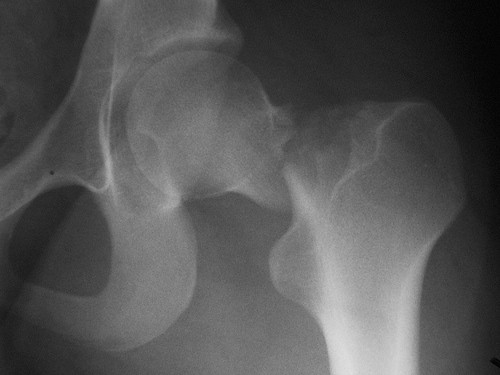

El tratamiento con incretinas no redujo el riesgo de fracturas

Una revisión de grandes cohortes poblacionales no confirmó el supuesto efecto protector de estos fármacos, que se había detectado en los ensayos clínicos aleatorizados. British Journal of Clinical Pharmacology, 7 de diciembre de 2016